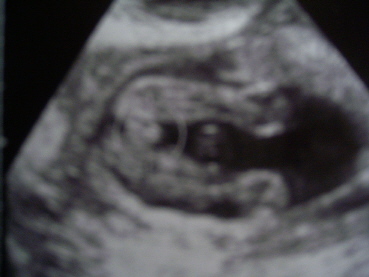

Pocaktesó

Lány létemre nem vagyok szégyenlős:)